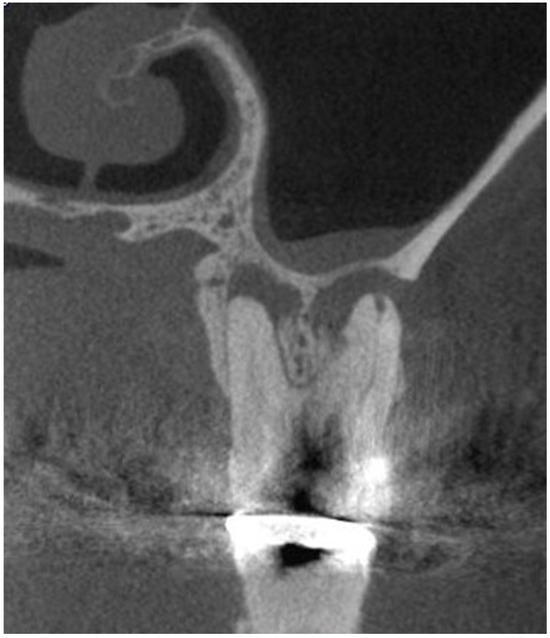

2. Materials and Methods

2.1. Evaluation of Dental Parameters